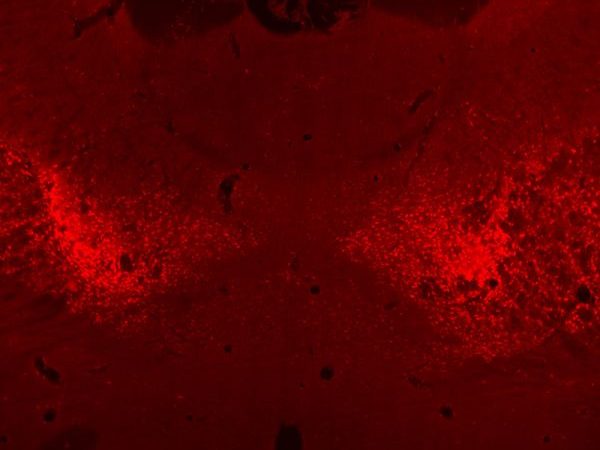

Substantia Nigra, Lan Hoang-Minh